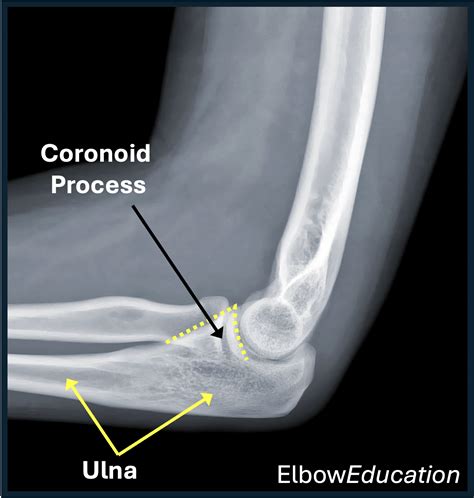

To truly grasp the significance of the ulnar coronoid process, one must first understand its structural position. The ulna is the bone on the medial side of the forearm (the side of the little finger). The proximal end of the ulna features a large notch known as the trochlear notch, which articulates with the trochlea of the humerus. The ulnar coronoid process forms the anterior (front) part of this notch.

This structure is triangular in shape and provides a stable surface for the elbow joint to pivot around. Because of its location, it acts as a physical barrier that prevents posterior (backward) displacement of the ulna relative to the humerus. If this structure is damaged, the entire joint becomes significantly more prone to dislocation or instability.

The primary responsibility of the ulnar coronoid process is to provide anterior stability to the elbow. When the elbow is flexed, this bony process helps lock the ulna in place, preventing it from sliding backward. Furthermore, it serves as a critical attachment point for several important structures, including:

If you experience these symptoms following an impact to the arm, it is important to seek medical imaging, such as an X-ray or CT scan, to assess the integrity of the ulnar coronoid process.

Diagnosis usually begins with a physical examination to test the stability of the elbow. However, because the coronoid is tucked deep within the joint, traditional X-rays may miss subtle fractures. A CT scan is often the gold standard for providing a 3D reconstruction of the ulnar coronoid process, allowing surgeons to see the exact size and orientation of a fracture fragment.